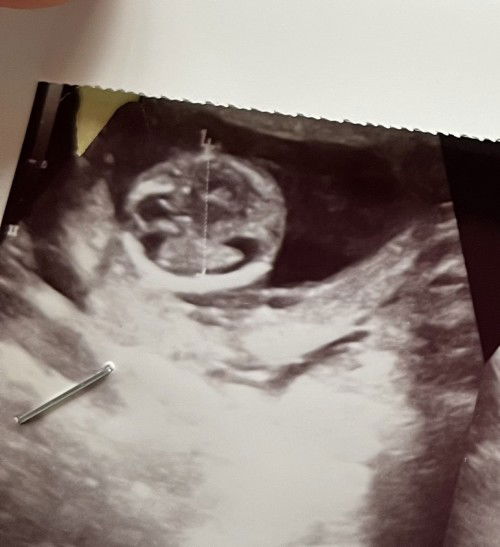

Hasil usg 15 week . Tanya hasil usg

Bun maaf mau tanya lingkaran bulat di gambar usg itu apa ya ? Karna dok ku hari itu buru buru ga sempet jelasin huhu #ingintahu #pleasehelp #firstmom #firstbaby